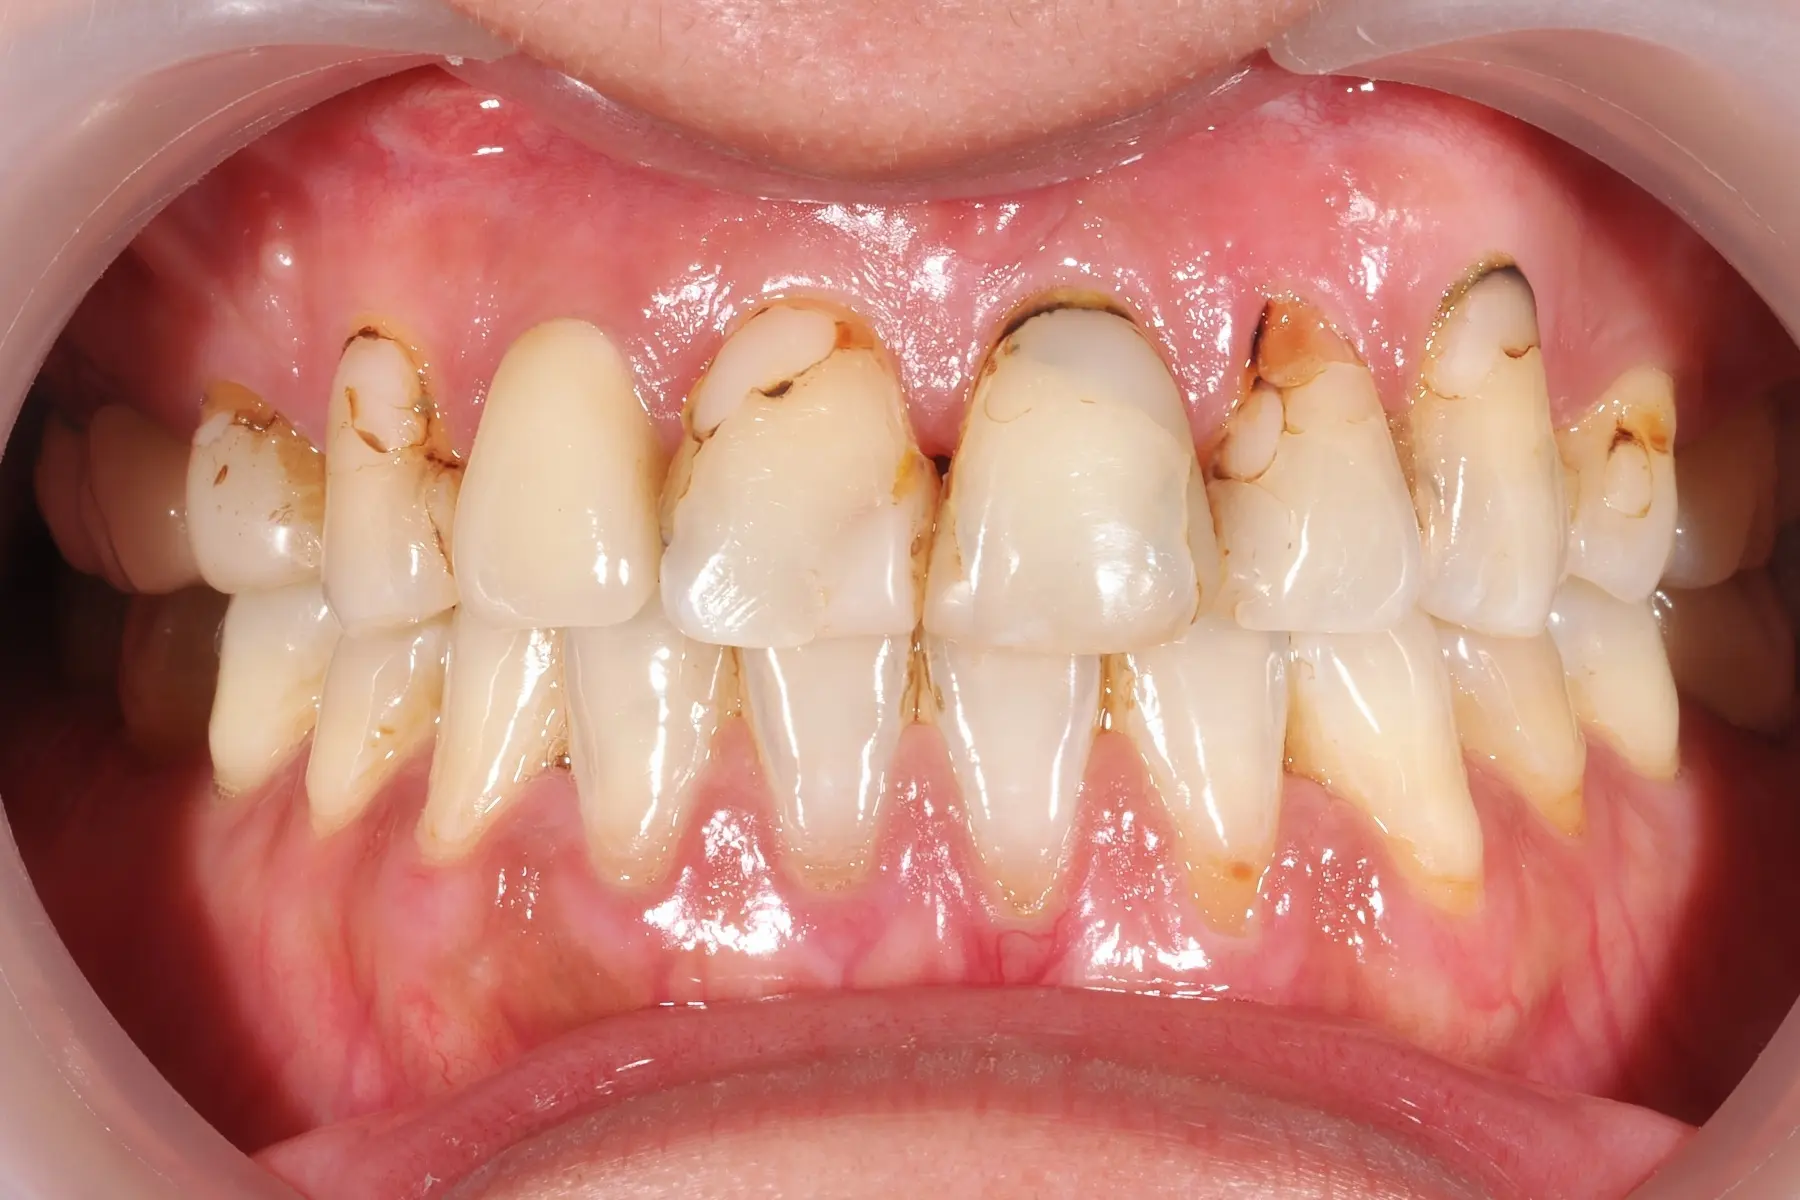

• 術前 42

術後 40

牙周治療

主治醫師

• 鍾國耀

治療時間

三次療程

主訴

牙齦紅腫出血、牙縫容易塞食物